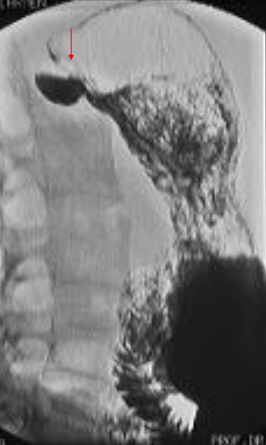

Achalazia cardiei